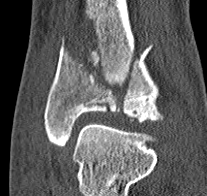

CT after external fixation application

CT scan

Commonly 3 fracture configurations

- medial malleolus

- posterolateral fragment / Volkmann

- anterolateral fragment / Chaput

- syndesmotic equivalent injuries more common with Chaput (AITFL Ligament) / Volkmann fragments (PITFL) or fibular avulsion